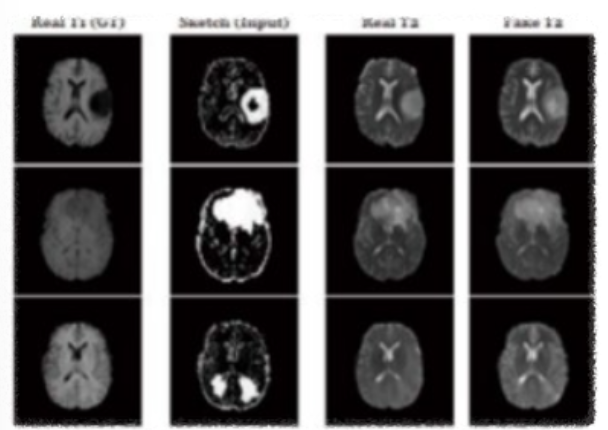

딥페이크 기술은 의료 교육에서 복잡한 수술을 시뮬레이션 하거나, 환자의 상태를 시각화하는 데 사용될 수 있다. 이는 의료 전문가들에게 중요한 훈련 도구가 된다. 예를 들어, 의사가 수술 계획을 세울 때 환자의 3D 모델을 통해 예행연습을 할 수 있다. 예를 들어, 2019년 7월 독일 뤼벡대학교 의료 정보학 연구소에서는 딥페이크 기술을 이용하여 다양한 암의 징후와 이상 시노를 탐지 가능한 모델을 개발했다.

세아3.png 딥페이크 기술 적용 의료 영상